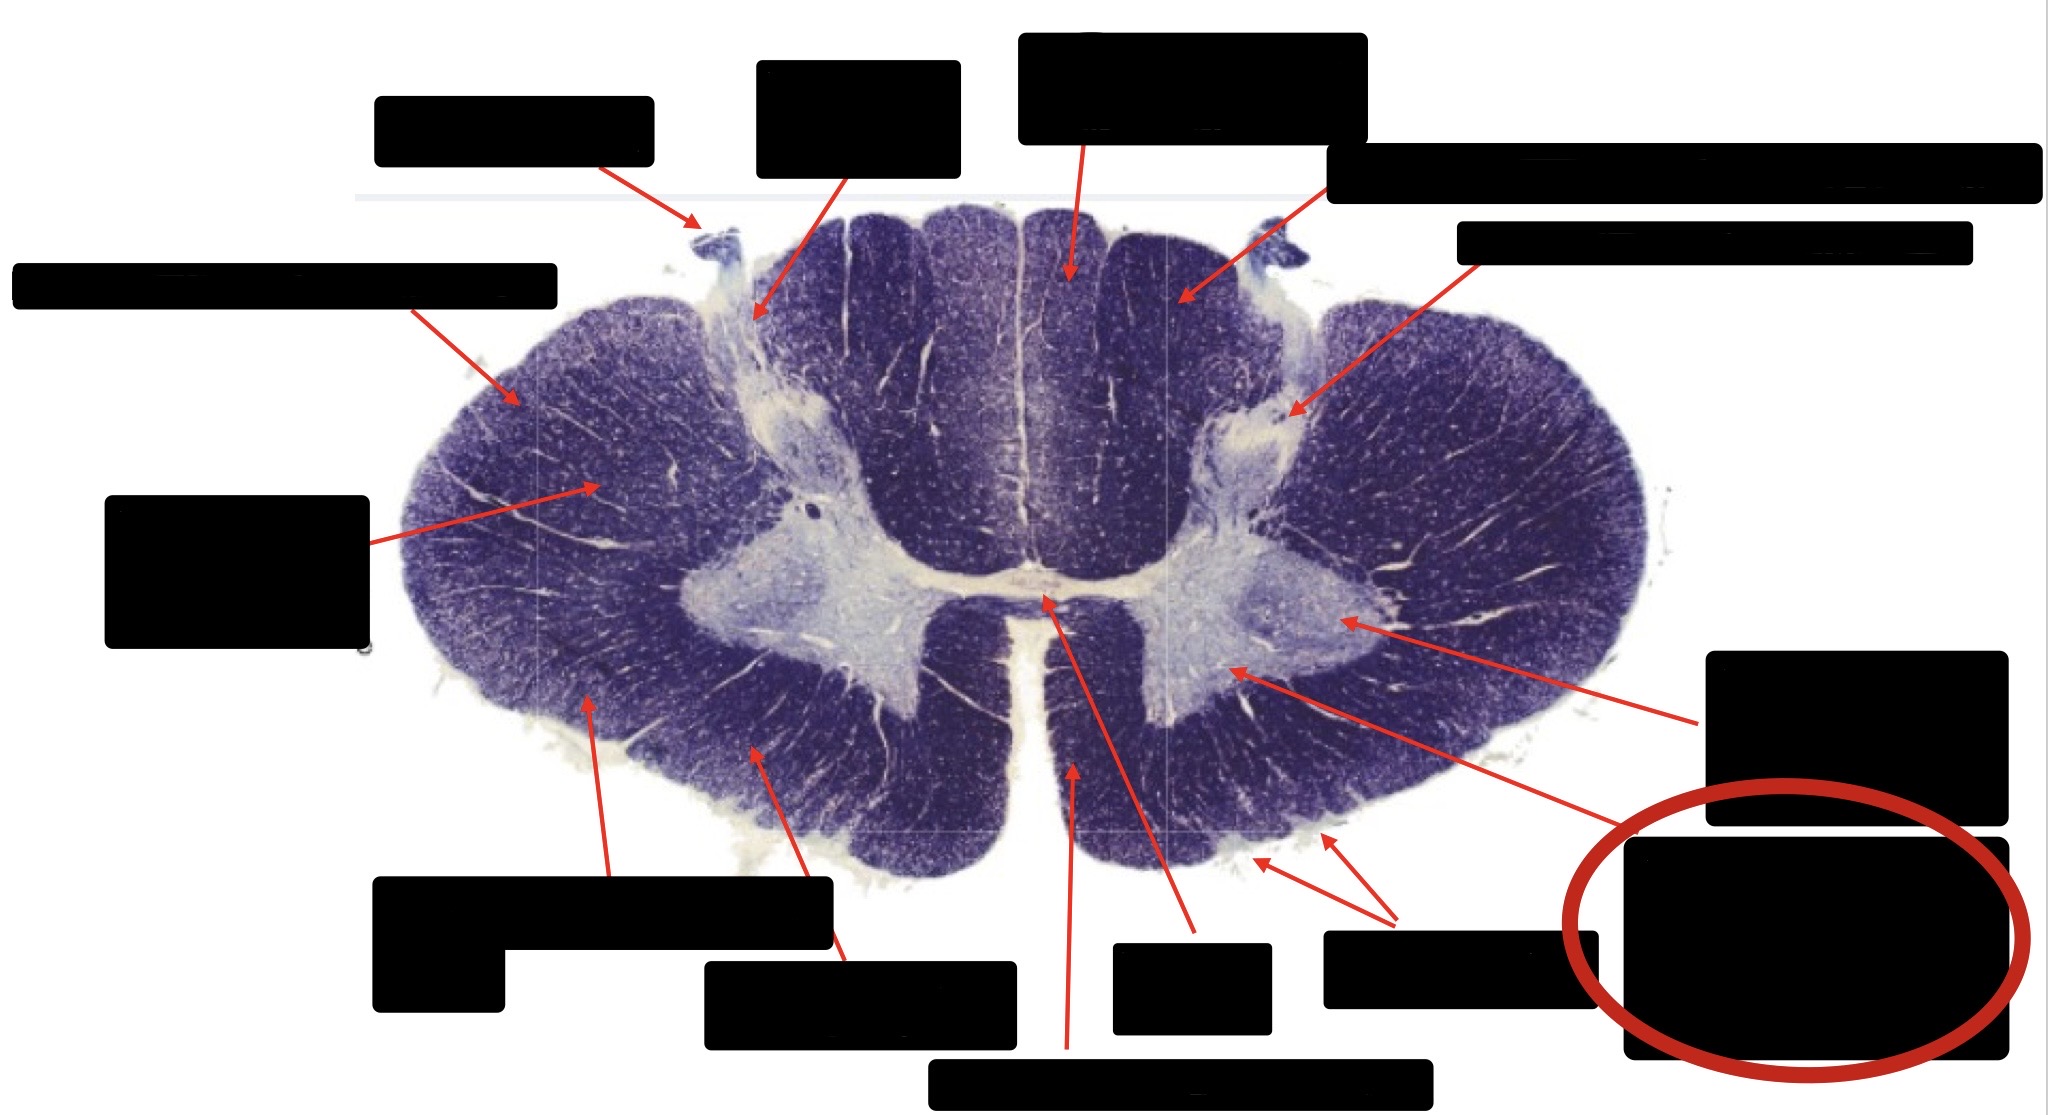

Central Canal

Anterior Corticospinal Tract

Posterior Column (Fasciculus Gracilis)

Posterior Column (Fasciculus Cuneatus)

Substantia Gelatinosa

Accessory Nerve Fibers

Anterior Horn Motor Fibers (Accessory Muscles)

Anterior Horn Motor Fibers (Proximal Muscles)

Ventral Root Fibers

Anterior Horn Motors Neurons (Proximal Muscles)

Posterior Columns (Joint Position, Vibration, Pressure)

Fasciculus Cuneatus

Fasciculus Gracilis

Dorsal Root

Dorsal Spinocerebellar Tract

Ventral Spinocerebellar Tract

Lateral Spinocerebellar Tract (Pain & Temperature)

Ventral Root

Anterior Horn (Motor Neurons)

Distal Limb Movements

Lateral Corticospinal (Pyramidal Tract)

Rubrospinal Tract

Axial & Proximal Limb Movements

Lateral Reticulospinal Tract

Vestibulospinal Tract

Ventral Reticulospinal Tract

Tectospinal Tract

Ventral Spinthalamic Tract (Pressure Touch - Minor Role)

Ventral (Uncrossed) Corticospinal Tract (Distal Limb Movements - Minor Role)